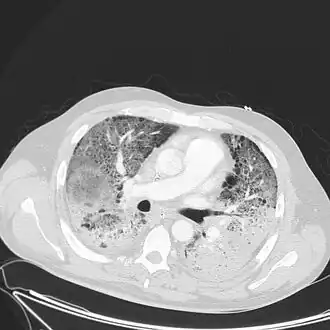

Medical imaging

Radiologic imaging has long been a criterion for diagnosis of ARDS. Original definitions of ARDS specified that correlative chest X-ray findings were required for diagnosis, the diagnostic criteria have been expanded over time to accept CT and ultrasound findings as equally contributory. Generally, radiographic findings of fluid accumulation (pulmonary edema) affecting both lungs and unrelated to increased cardiopulmonary vascular pressure (such as in heart failure) may be suggestive of ARDS. Ultrasound findings suggestive of ARDS include the following:

- bilateral opacities on chest imaging (chest radiograph or CT) not explained by other lung pathology (e.g. effusion, lobar/lung collapse, or nodules)